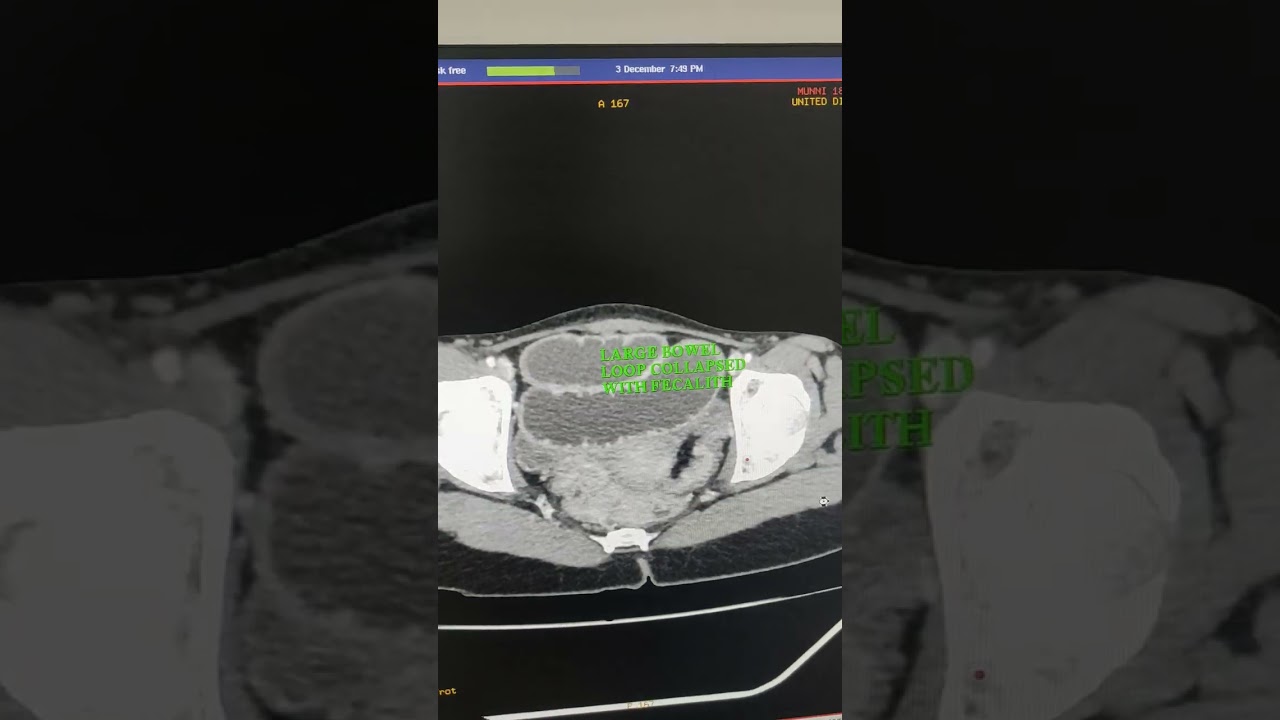

Скачать или смотреть stricture in ileum stomach and duodenum junction are collepsed and collepsed of large bowel loops

stricture in ileum stomach and duodenum junction are collepsed and collepsed of large bowel loops